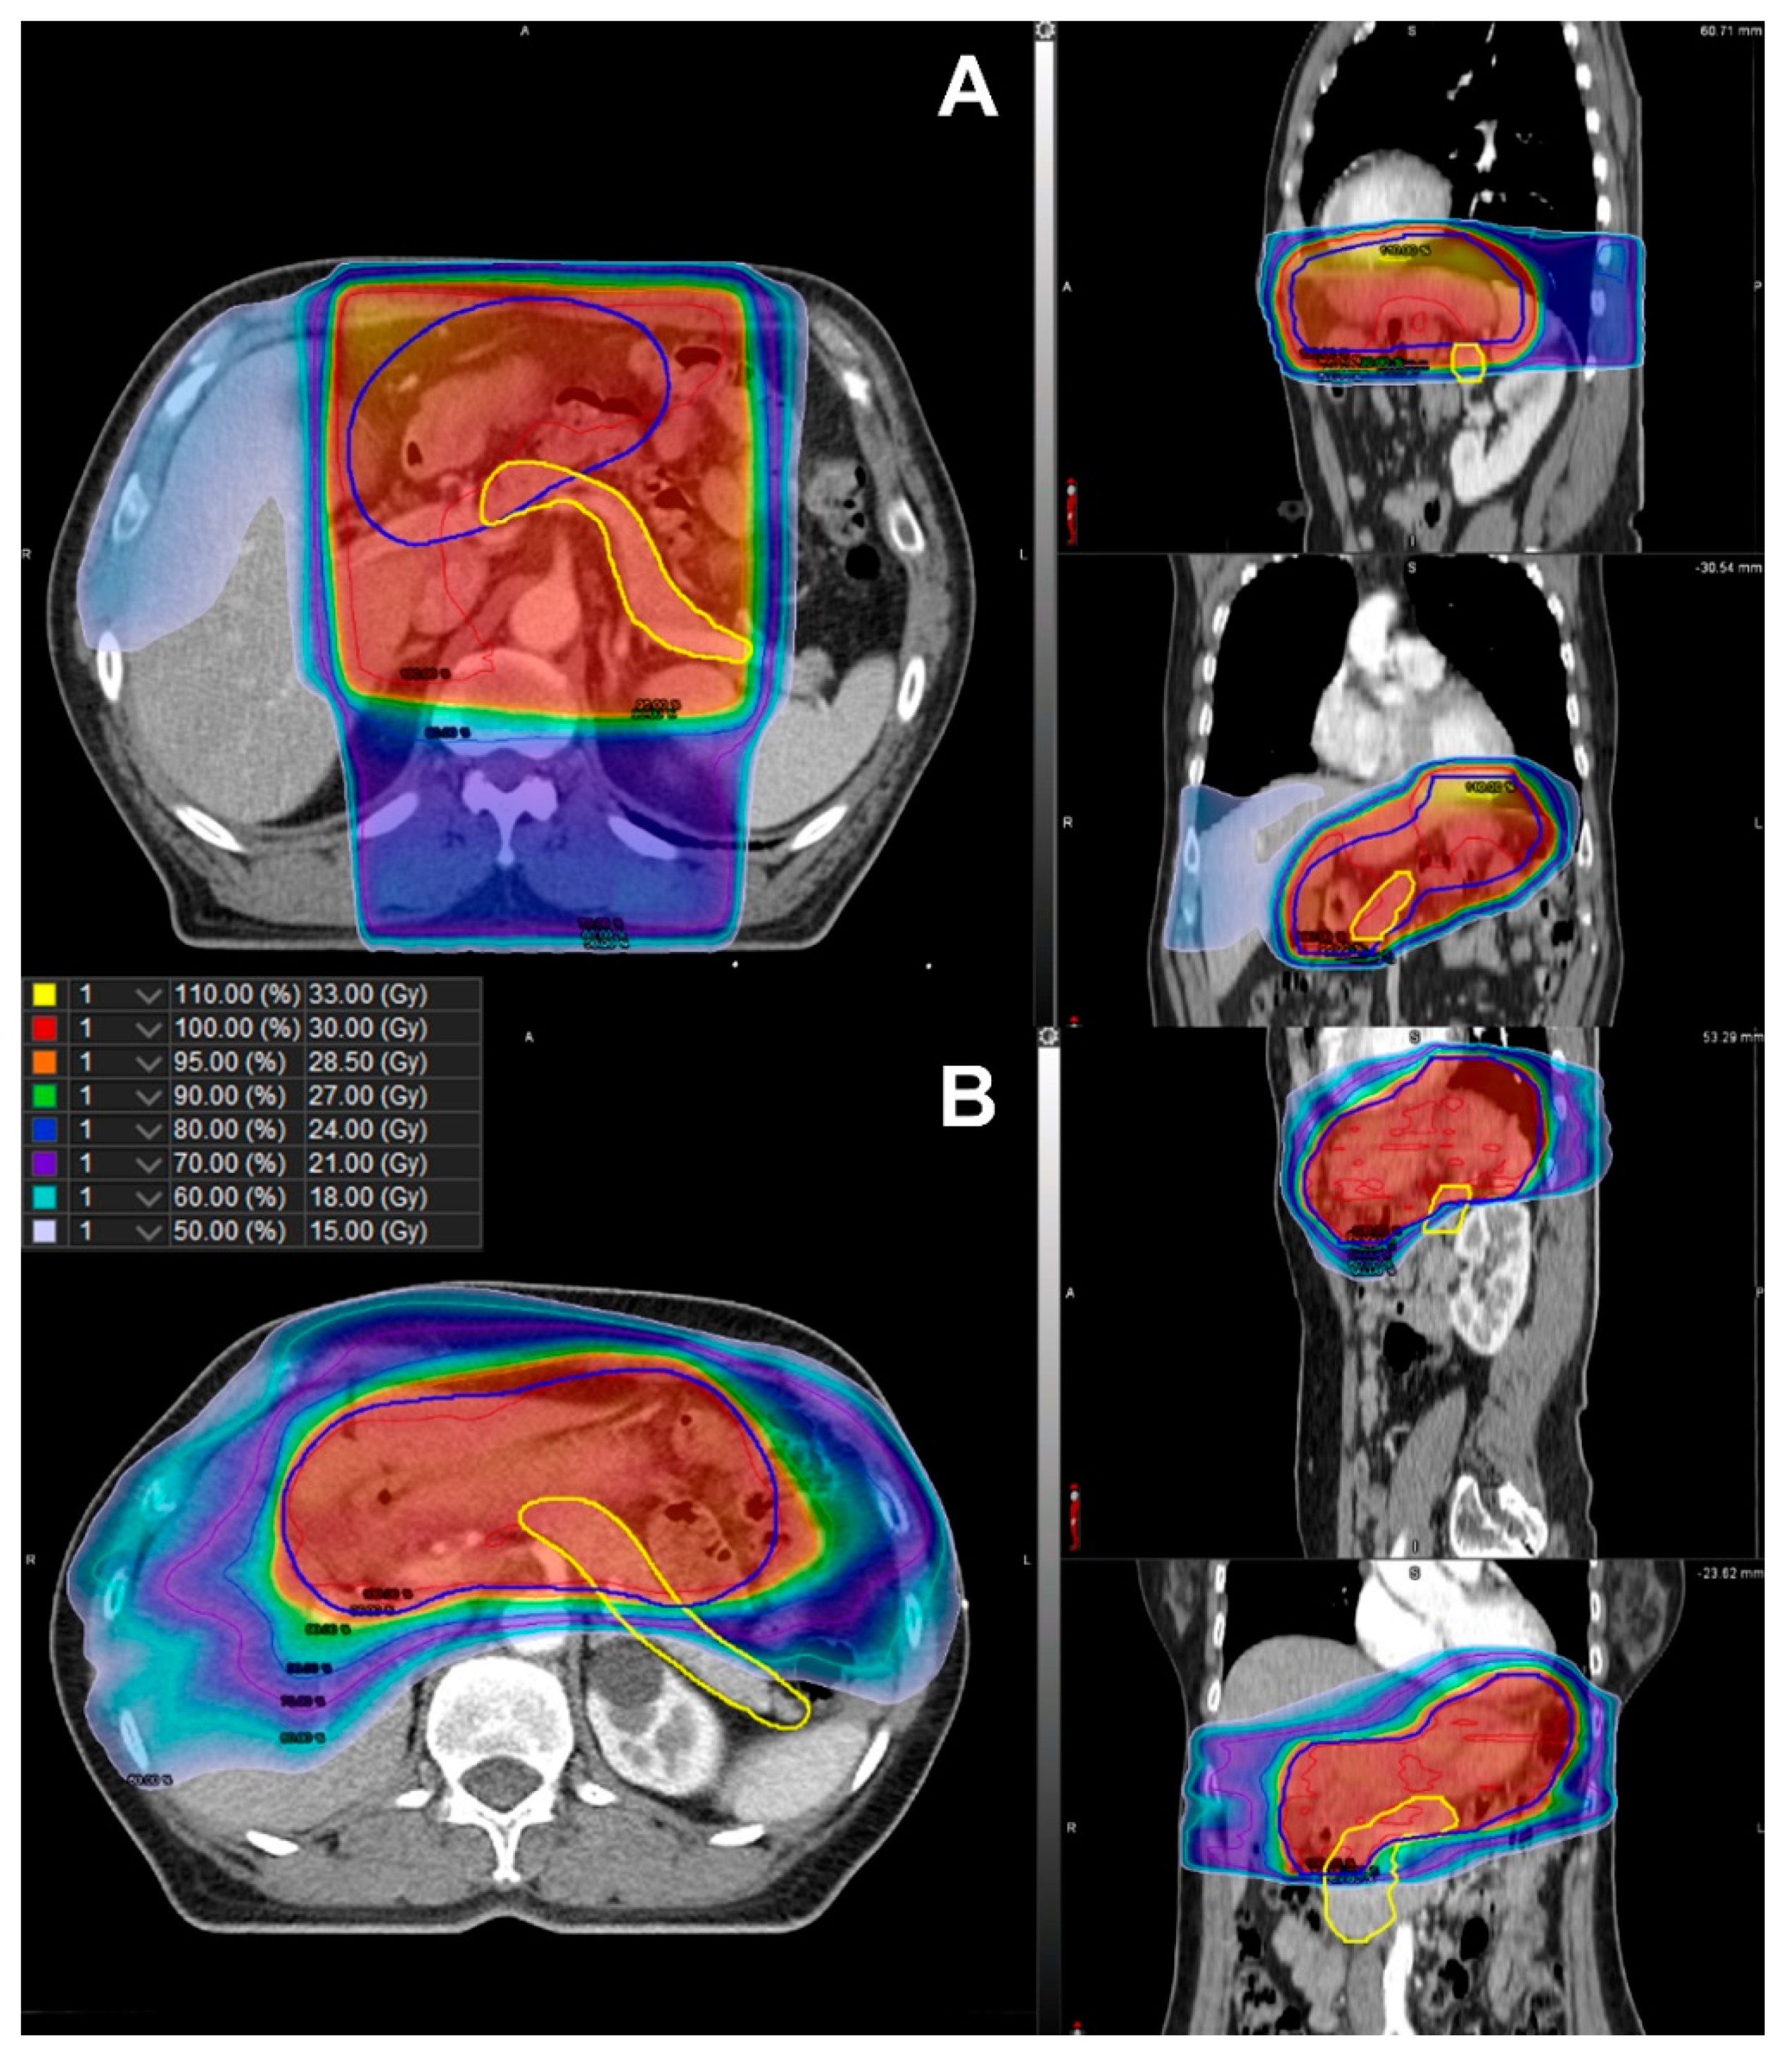

Further, RPA stratified the patients according to their risk of developing DM (Figure 2). Among the clinical factors and dosimetric parameters, patients were initially split between Dmean < 21.0 Gy and Dmean ≥ 21.0 Gy. Representative isodose distributions for a patient with Dmean ≥ 21.0 Gy using 3D-CRT and a patient with Dmean < 21.0 Gy using IMRT are presented in Figure 3. The split groups were further divided into BMI < 25.0 kg/m2 and BMI ≥ 25.0 kg/m2. The group with Dmean ≥ 21.0 Gy and BMI < 25.0 kg/m2 was once again stratified by sex. The patients with Dmean < 21.0 Gy and BMI < 25.0 kg/m2 were defined as the low-risk group (n = 102; Figure 2). Among the patients with Dmean ≥ 21.0 Gy, those with BMI ≥ 25.0 kg/m2 or male patients with BMI <25.0 kg/m2 were defined as high-risk (n = 49; Figure 2). Those patients who were not included in either the low- or high-risk groups were defined as the intermediate-risk group (n = 74; Figure 2). The 5-year cumulative incidence of DM was 0.0% (95% CI 0.0–0.0%), 3.1% (95% CI 0.8–12.3%), and 15.6% (95% CI 7.8–31.3%) in the low-, intermediate-, and high-risk groups, respectively (Figure 4, p < 0.001). The cumulative incidence of DM in the low- and intermediate-risk groups was significantly lower than that in the high-risk group (low vs. high, p < 0.001; intermediate vs. high, p = 0.020), while the difference between the low- and intermediate-risk groups was not statistically significant (p = 0.095).

Figure 3. Comparison of isodose distribution of the planning target volume (blue line) and the pancreas (yellow line) in (A) three-dimensional conformal radiotherapy with Dmean ≥ 21.0 Gy and (B) intensity-modulated radiotherapy with Dmean < 21.0 Gy. Dmean, mean dose in gray irradiated to the whole pancreas.